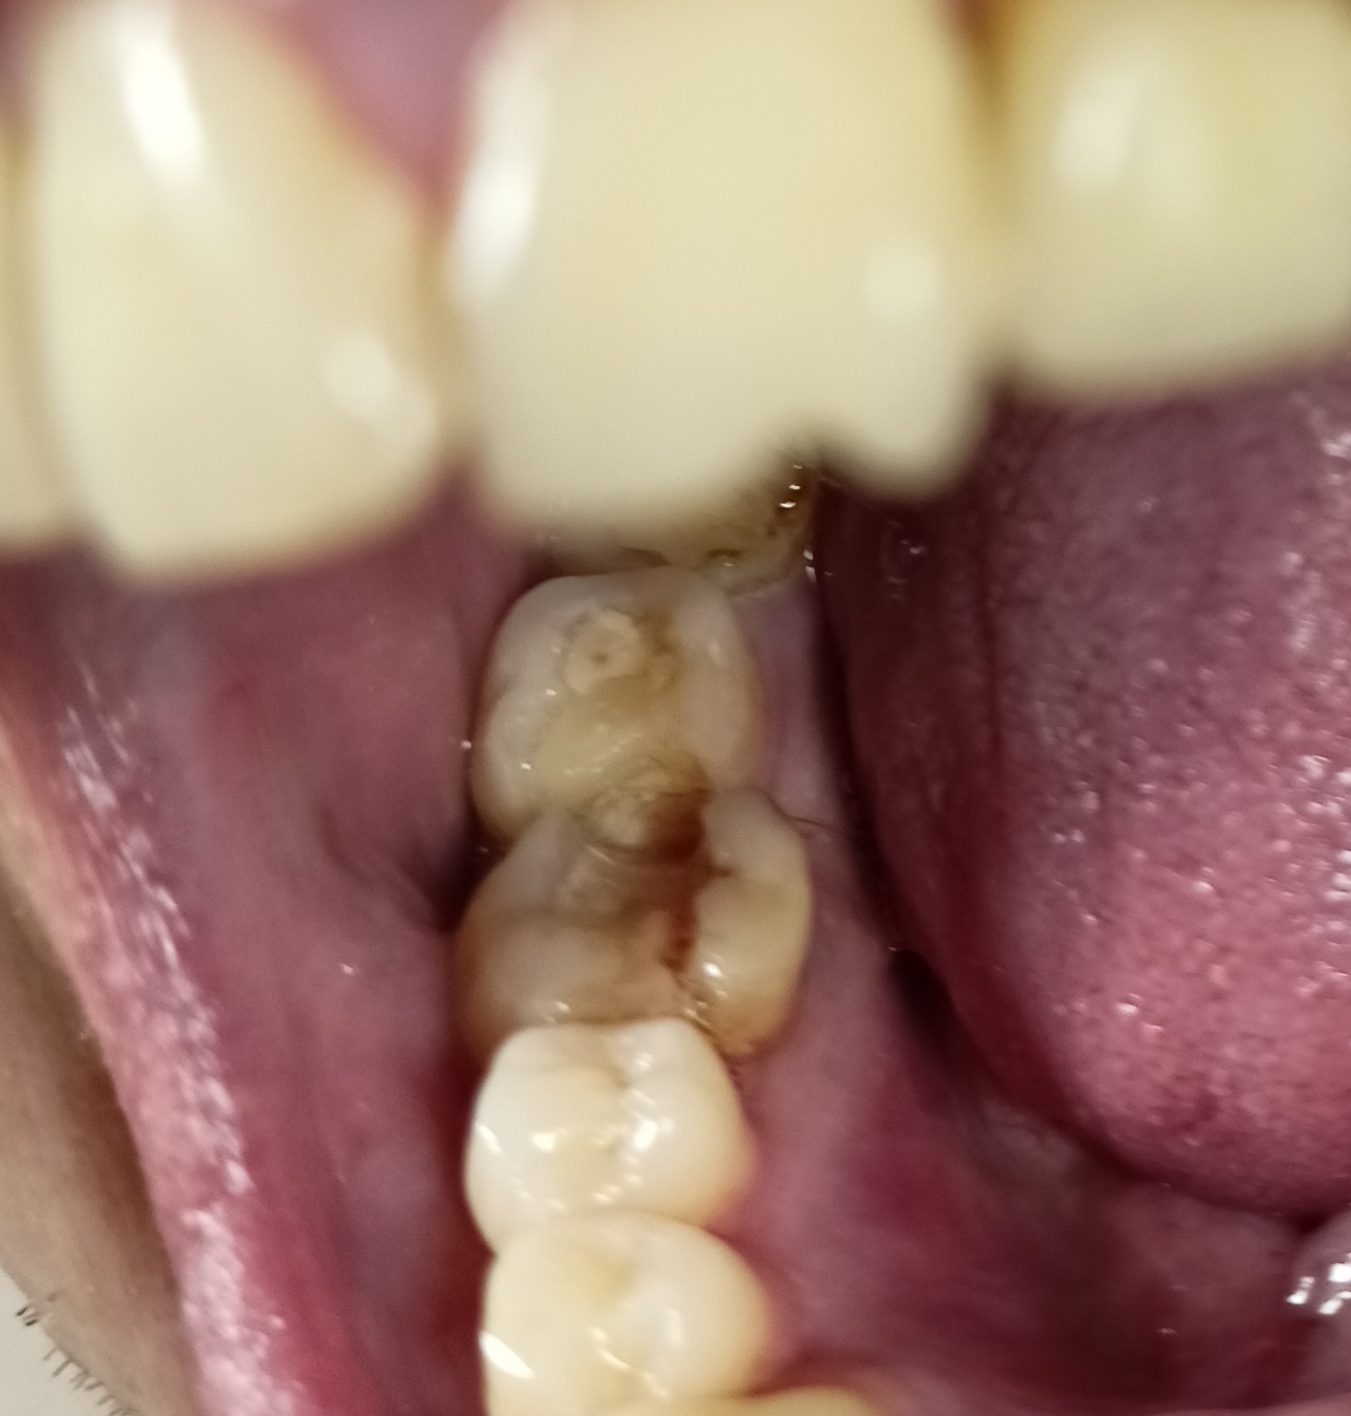

IMG202509231641[...].jpg 618Кб, 2872x992

2872x992

тут есть какое воспаление или что то что может вызвать боль?